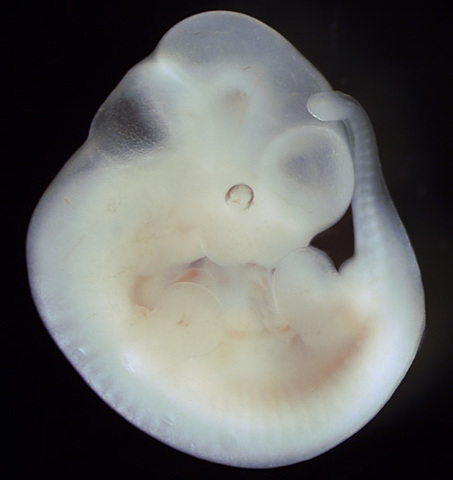

• 43-50 DÍAS – SÉPTIMA SEMANA

43-50 DÍAS – SÉPTIMA SEMANA

Se logra diferenciar regiones del cuerpo.

Aparecen los dedos.

El embrión crece rápidamente, pasa de 5 mm a 13 mm.

El corazón tiene ya dos cámaras

Los pulmones tienen un bronquio primario.

El cerebro se divide en dos hemisferios.

Aparecen fosas nasales y órbitas de los ojos.

La placenta sigue en estabilización, aunque aun no sirve de suministro.